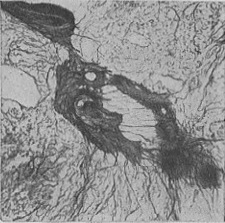

Рідше зустрічається дифузний миеломатоз, коли дифузне розростання мієломних клітин не супроводжується розвитком вузлів. При цій формі тканина кісткового мозку на розрізі має строкатий вигляд, містить рожево-білі, сіро-червоні поля, спостерігається дифузний остеопороз; в рідкісних випадках розсмоктування кісткової тканини є незначним. При гістологічному дослідженні кісткового мозку виявляють розростання ретикулярних клітин різної величини і форми, часто плазматического типу з базофильной цитоплазмою, багатою РНК; зустрічаються гігантські багатоядерні клітини. В області розростань завжди виявляється ніжна мережа аргірофільних волокон (рис. 7).

![]() Рис. 7. Миеломный вузол в кістковому мозку з вираженою мережею аргірофільних волокон (імпрегнація сріблом за Футу). |